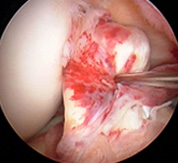

損傷した前十字靭帯